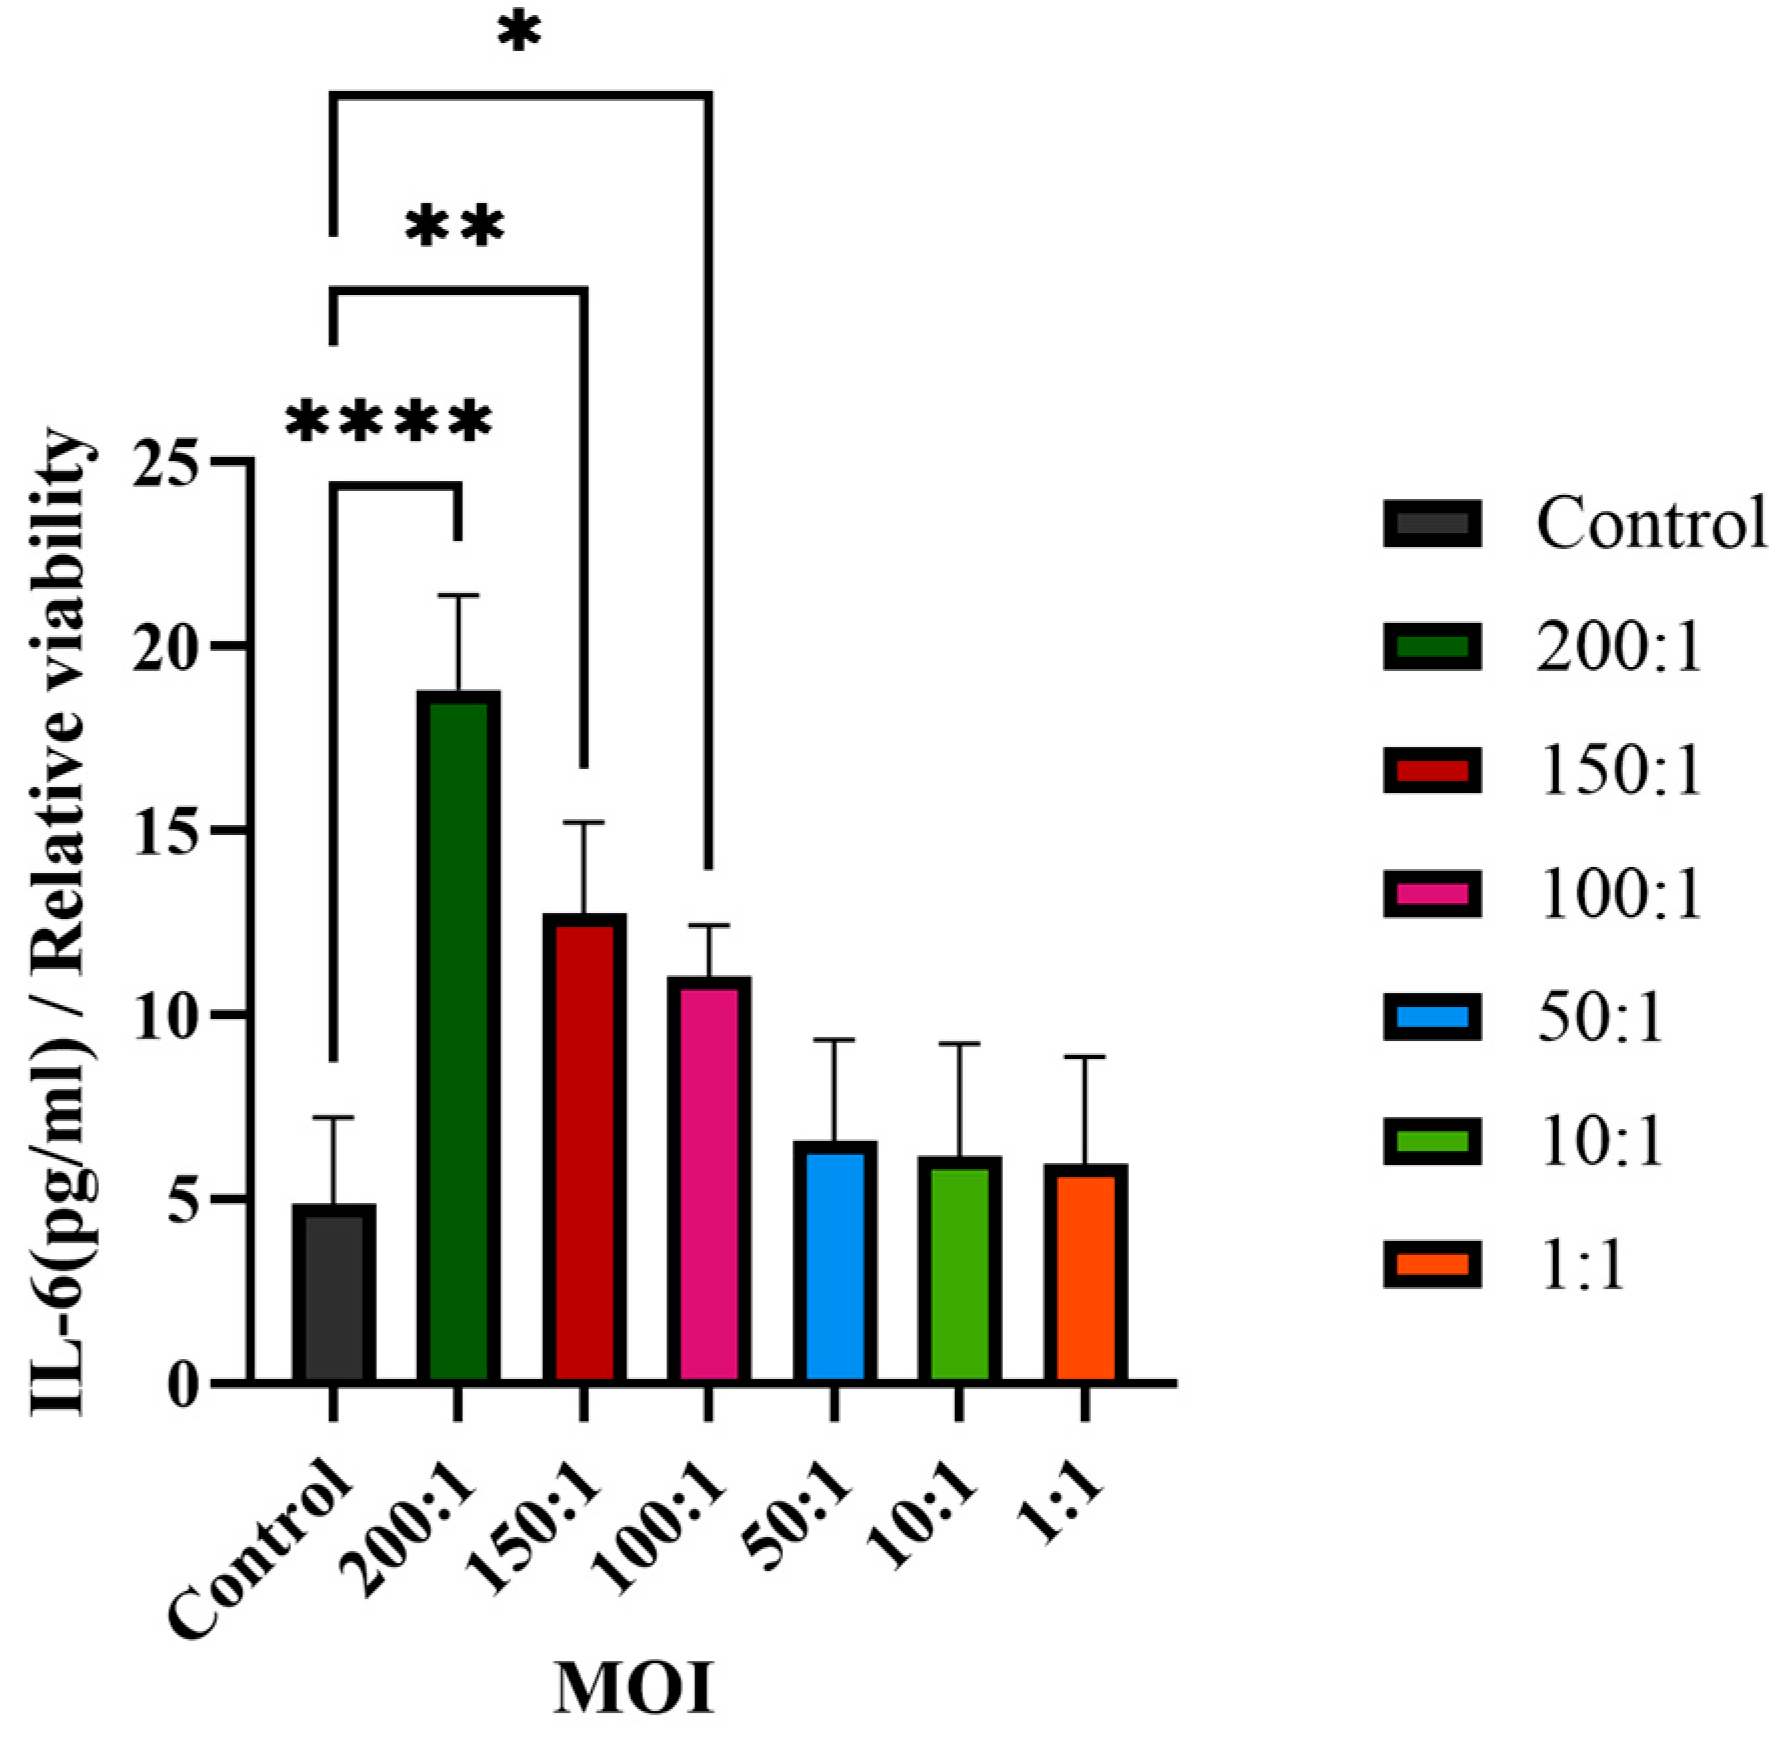

2.10. Pro-Inflammatory Cytokine Using ELISA Assay

The supernatant collected above (

Section 2.9) was used to determine the IL-6 secretion without dilution using an ELISA immunoassays kit (Beijing Shengyan Biology, Beijing, China). The secretion of the pro-inflammatory cytokine IL-6 was determined by ELISA according to the manufacturer’s protocol, with a linearity range of 1.5–48 pg/mL. Three technical replicates were performed for each sample. The absorbance value of each sample was measured at 450 nm using a Spark Multimode Microplate Reader (Tecan Trading AG, Shanghai, China).

2.11. Calculation of the Cytokine Secretion

In order to reduce any variation due to the differences in cell density, the normalized cytokine secretion values were adjusted by the cell viability using the following equation:

The cells not treated with C. acnes IA1 were designated as the control group, which had a viability of 1, and the relative viability of the treated groups was compared to that of the control group.

Central to our findings are the hub genes HNRNPA2B1, HNRNPM, and RBM39, identified through the protein–protein interaction (PPI) network analysis as key regulators of acne pathogenesis. HNRNPA2B1, a heterogeneous nuclear ribonucleoprotein, modulates RNA splicing and stability, and its upregulation in infected keratinocytes may enhance the expression of pro-inflammatory transcripts, such as those encoding cytokines like IL-6 [

22]. This is consistent with our observation of significantly elevated IL-6 levels (

p < 0.01), a cytokine known to promote keratinocyte proliferation and sebocyte differentiation in acne [

10]. The significant increase in IL-6 secretion validates the transcriptomic upregulation of IL-6 signaling and aligns with hub gene functions, as HNRNPA2B1 and RBM39 regulate cytokine expression through splicing [

22]. These findings highlight IL-6 as a pivotal mediator of acne inflammation, suggesting that targeting its upstream regulators or CLR signaling could mitigate

C. acnes IA

1–induced damage. Furthermore, the cutaneous microenvironment and its extracellular matrix (ECM) components play a crucial role in modulating inflammatory responses to microbial stimuli, such as